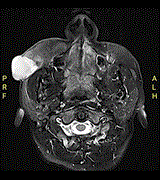

Image-guided endonasal endoscopic excision of Meckel’s cave trigeminal schwannoma from cavernous and petrous carotid artery

Ali Almomen and others

Journal of Surgical Case Reports, Volume 2020, Issue 9, September 2020, rjaa374, https://doi.org/10.1093/jscr/rjaa374